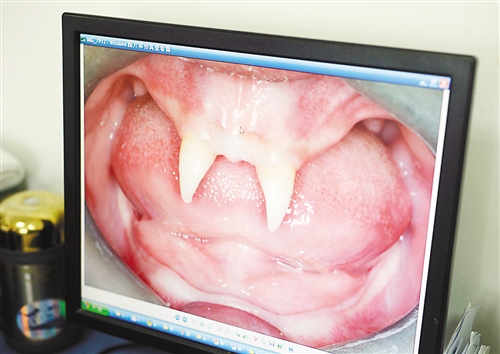

12月18日,16歲的張成(化名)從小到大,只有上顎部分有兩顆牙,看上去更像長(zhǎng)著一對(duì)獠牙。 記者熊明攝

重慶日?qǐng)?bào)訊 每個(gè)人都有牙齒,但對(duì)16歲的張成(化名)來說,從小到大,他只有上顎部分有兩顆牙,看上去更像長(zhǎng)著一對(duì)獠牙,這讓他很自卑又易怒。12月18日,在母親的陪同下,他來到三軍醫(yī)大西南醫(yī)院求助。經(jīng)醫(yī)生檢查,發(fā)現(xiàn)張成患有一種罕見的基因病。

張成是貴州銅仁地區(qū)思南縣人,從生下來就似乎得了一種怪病,身上毛發(fā)稀少,面部發(fā)育也不好。更奇怪的是,別人家的孩子都長(zhǎng)牙吃東西了,他卻一直長(zhǎng)不出牙齒,最后只在上顎部分冒出兩顆比較突出且對(duì)稱的牙齒,看起來就像一對(duì)獠牙。